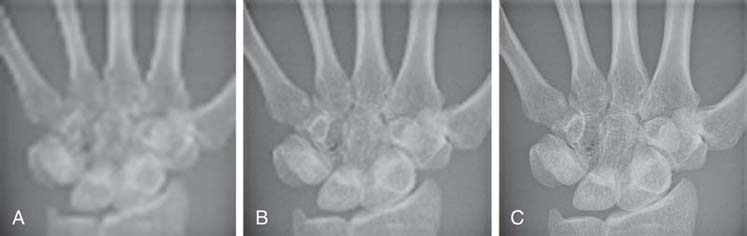

Spatial resolution in digital imaging is primarily limited to the size of the pixel; however, when measuring an imaging system's ability to resolve small objects, it is important to understand the concept of spatial frequency and its relationship with spatial resolution. Spatial frequency can be defined by the unit of line pairs per millimeter (lp/mm). A resolution test pattern is a device used to record and measure line pairs (Fig. 4-6). Anatomic details are composed of large and small objects, and radiographic images display these details as variations from white to black brightness levels. Small objects have higher spatial frequency, and large objects have lower spatial frequency. It is more difficult to accurately image small anatomic objects (high spatial frequency) than to image large ones (low spatial frequency). An imaging system that can resolve a greater number of lp/mm (higher spatial frequency) has increased spatial resolution (Fig. 4-7). In digital imaging systems, the ability to resolve or demonstrate a specific spatial frequency is directly impacted by the size of the pixel. The images of the wrist (Fig. 4-8) demonstrate the impact that pixel size has on the spatial resolution visualized in an image.

FIG. 4-8 Images showing how pixel size affects spatial resolution. A, Image with 20 pixels/cm; therefore, the pixel size is larger, and the spatial resolution is poor. B, Image with 40 pixels/cm. C, Image with 100 pixels/cm; therefore the pixel size is smaller than that in images A and B, and the spatial resolution is improved. (Courtesy of Andrew Woodward.)